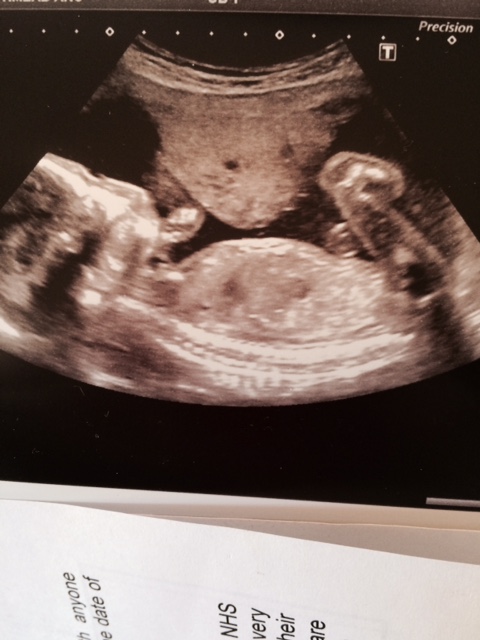

Hi there. I just wondered i the long white line at the bottom is a side view of the clitoris? I have seen other pictures like it that say tht's what the clitoris looks like side on at 20 weeks and I just wanted to know what you ladies thought? Many thanks.Attachment 25354